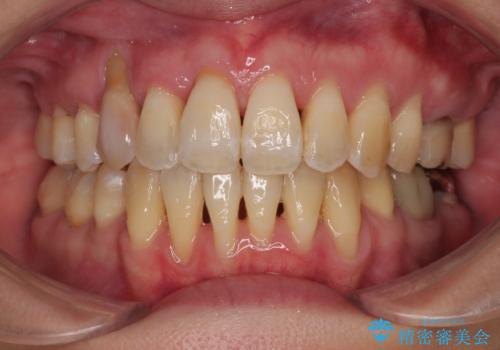

捻れて前に出ている前歯 ワイヤー装置での非抜歯矯正